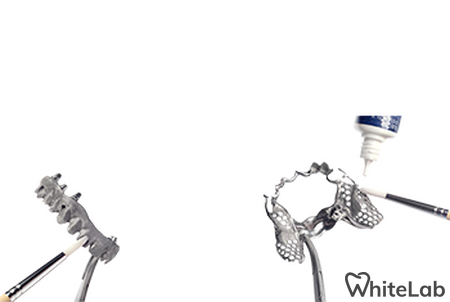

Мы изготавливаем безметалловые виниры и коронки методикой прессования керамики, фрезерование керамики и циркония для создание полной анотомии зуба. Так же используем технику нанесение керамики на рефракторе, при которой слои керамики укладываются послойно, у зуба восстанавливается полная анатомия и он выглядит как натуральный.

Данные методики дают возможность получить естественный, яркий, блестящий вид винирам, коронкам, которые создают самые естественные, реалистичные преобразования улыбки, которые могут быть достигнуты современными технологиями.